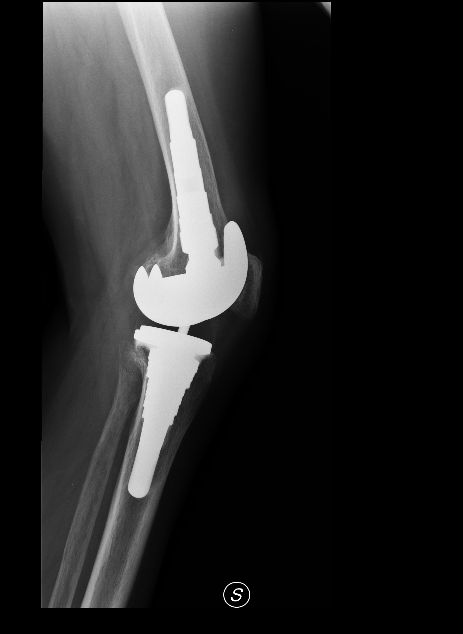

Da quando ha preso servizio presso l’Ospedale del Delta si è sempre occupato della chirurgia protesica del ginocchio sia monocompartimentale che totale acquisendo esperienza anche sulle tecniche basate sulla navigazione assistita che sull’impianto di protesi custom-made. Di routine esegue interventi di chirurgia artroscopica per il trattamento delle patologie meniscali e cartilaginee e di ricostruzione del legamento crociato anteriore mediante varie tecniche